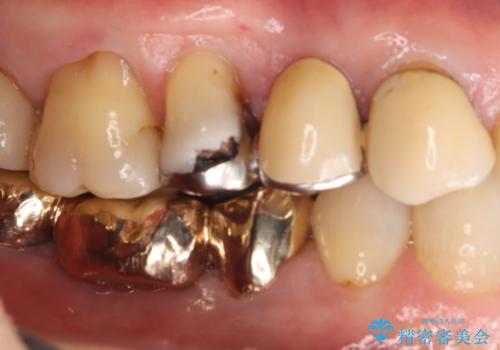

- 主訴:ブリッジの歯が一部欠けた

右上⑤4③でメタルフレームを用いたブリッジが既に入っており、その内右上5番目の歯がう蝕により欠けてしまっていました。

元々5番目の歯には4/5冠が入っていましたが、ブリッジのやり替えに際しクラウンとしました。